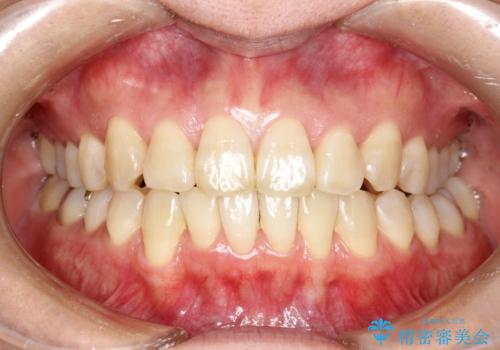

マウスピース枚数 初回52枚 + 追加19枚 + 追加12枚

概ね2年での治療完了となりました。

上の歯列に後方への力をかけるために、患者様には顎間ゴムをマウスピースと共に併用してもらいました。

当院独自の工夫を随所に盛り込み、狙い通りの治療結果が得られました。